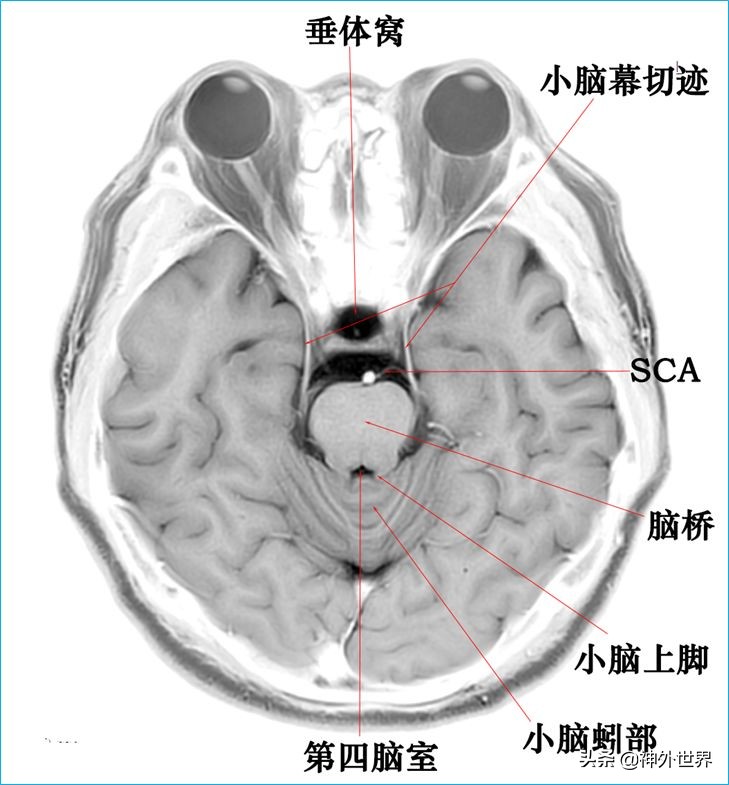

四、T2WI反相图学颅脑断层解剖

以下图片均来自我院3.0T核磁共振的T2WI反相图。标注均为我自己完成,水平有限,难免有误,还望各位老师多多指正。谢谢。